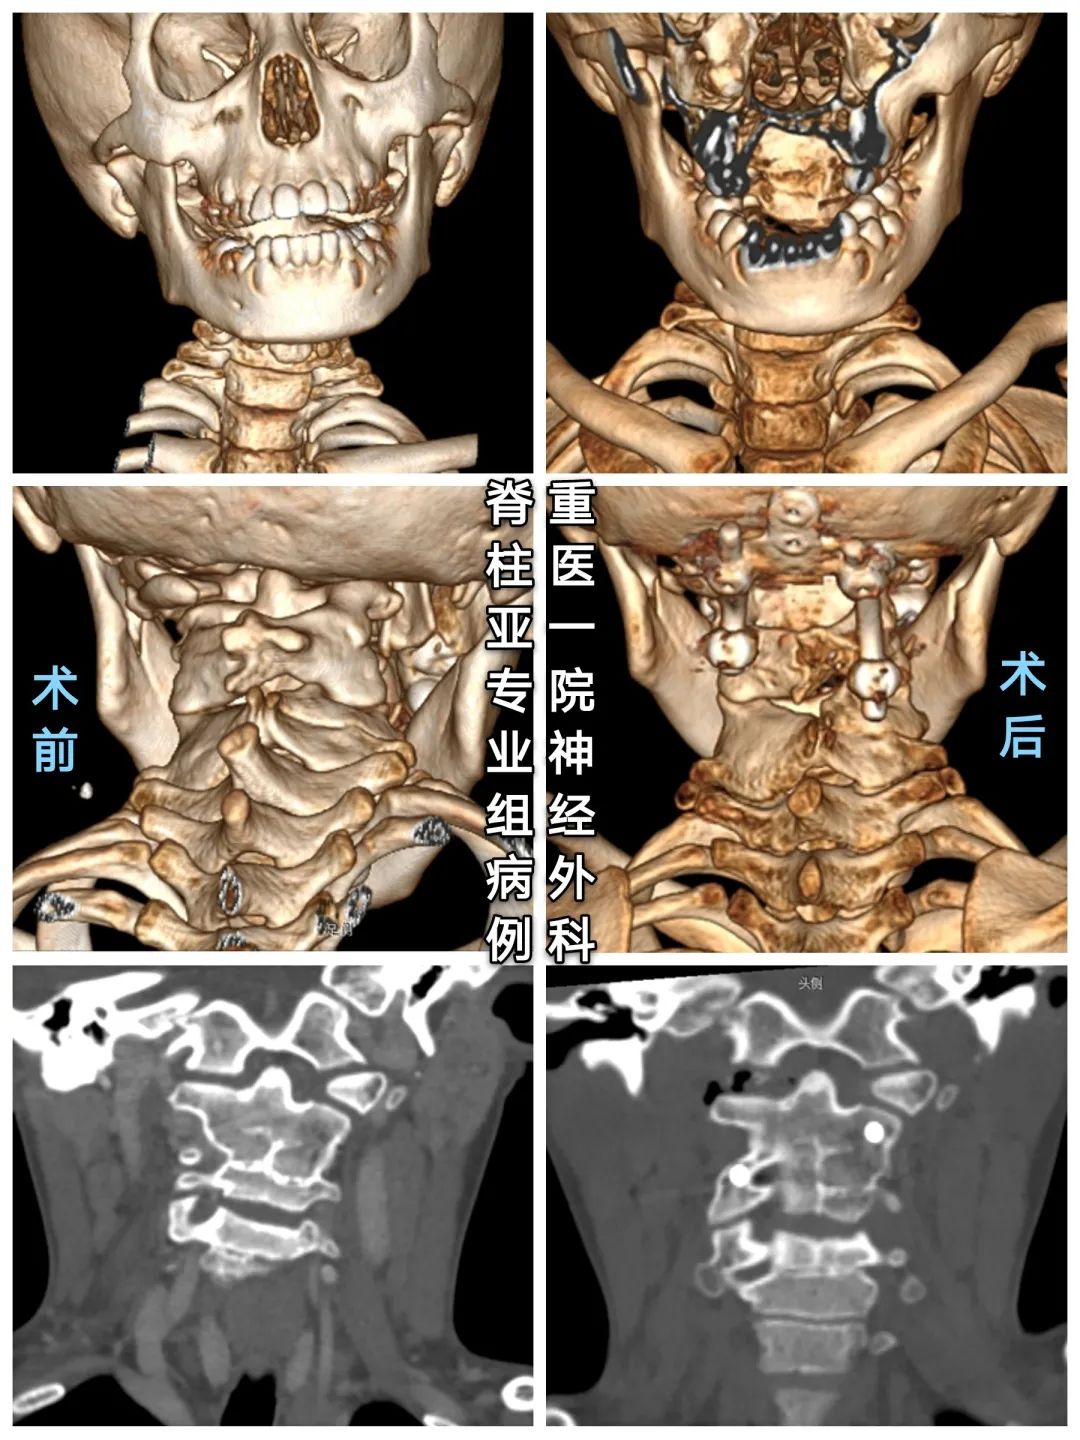

◆术前颈椎CT

寰椎右份缺如,与颈2、3椎体融合,颈4-6椎融合。

右椎动脉粗大,于颅颈部呈窗型(分3只血管后融合,其中一血管走行寰枢椎连接部间)

后路枕颈关节撑开矫形植骨融合内固定术